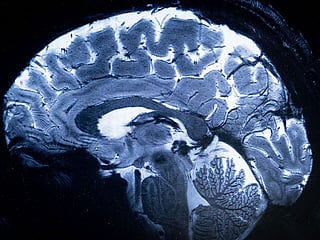

The rare and often fatal brain infection is caused by Naegleria fowleri, commonly known as the brain-eating amoeba. Cases have been recorded across multiple districts, affecting people from a three-month-old infant to a 91-year-old.

Primary Amoebic Meningoencephalitis, also known as naegleriasis, is a brain infection caused by the protozoan Naegleria fowleri. The amoeba thrives in warm freshwater such as ponds, lakes, and poorly chlorinated pools.

Once water enters the nose, the amoeba can travel to the brain, destroying tissue. Symptoms typically include headache, fever, nausea, vomiting, seizures, and hallucinations. It is not spread by drinking contaminated water or through person-to-person contact. The disease is almost always fatal if not diagnosed early.